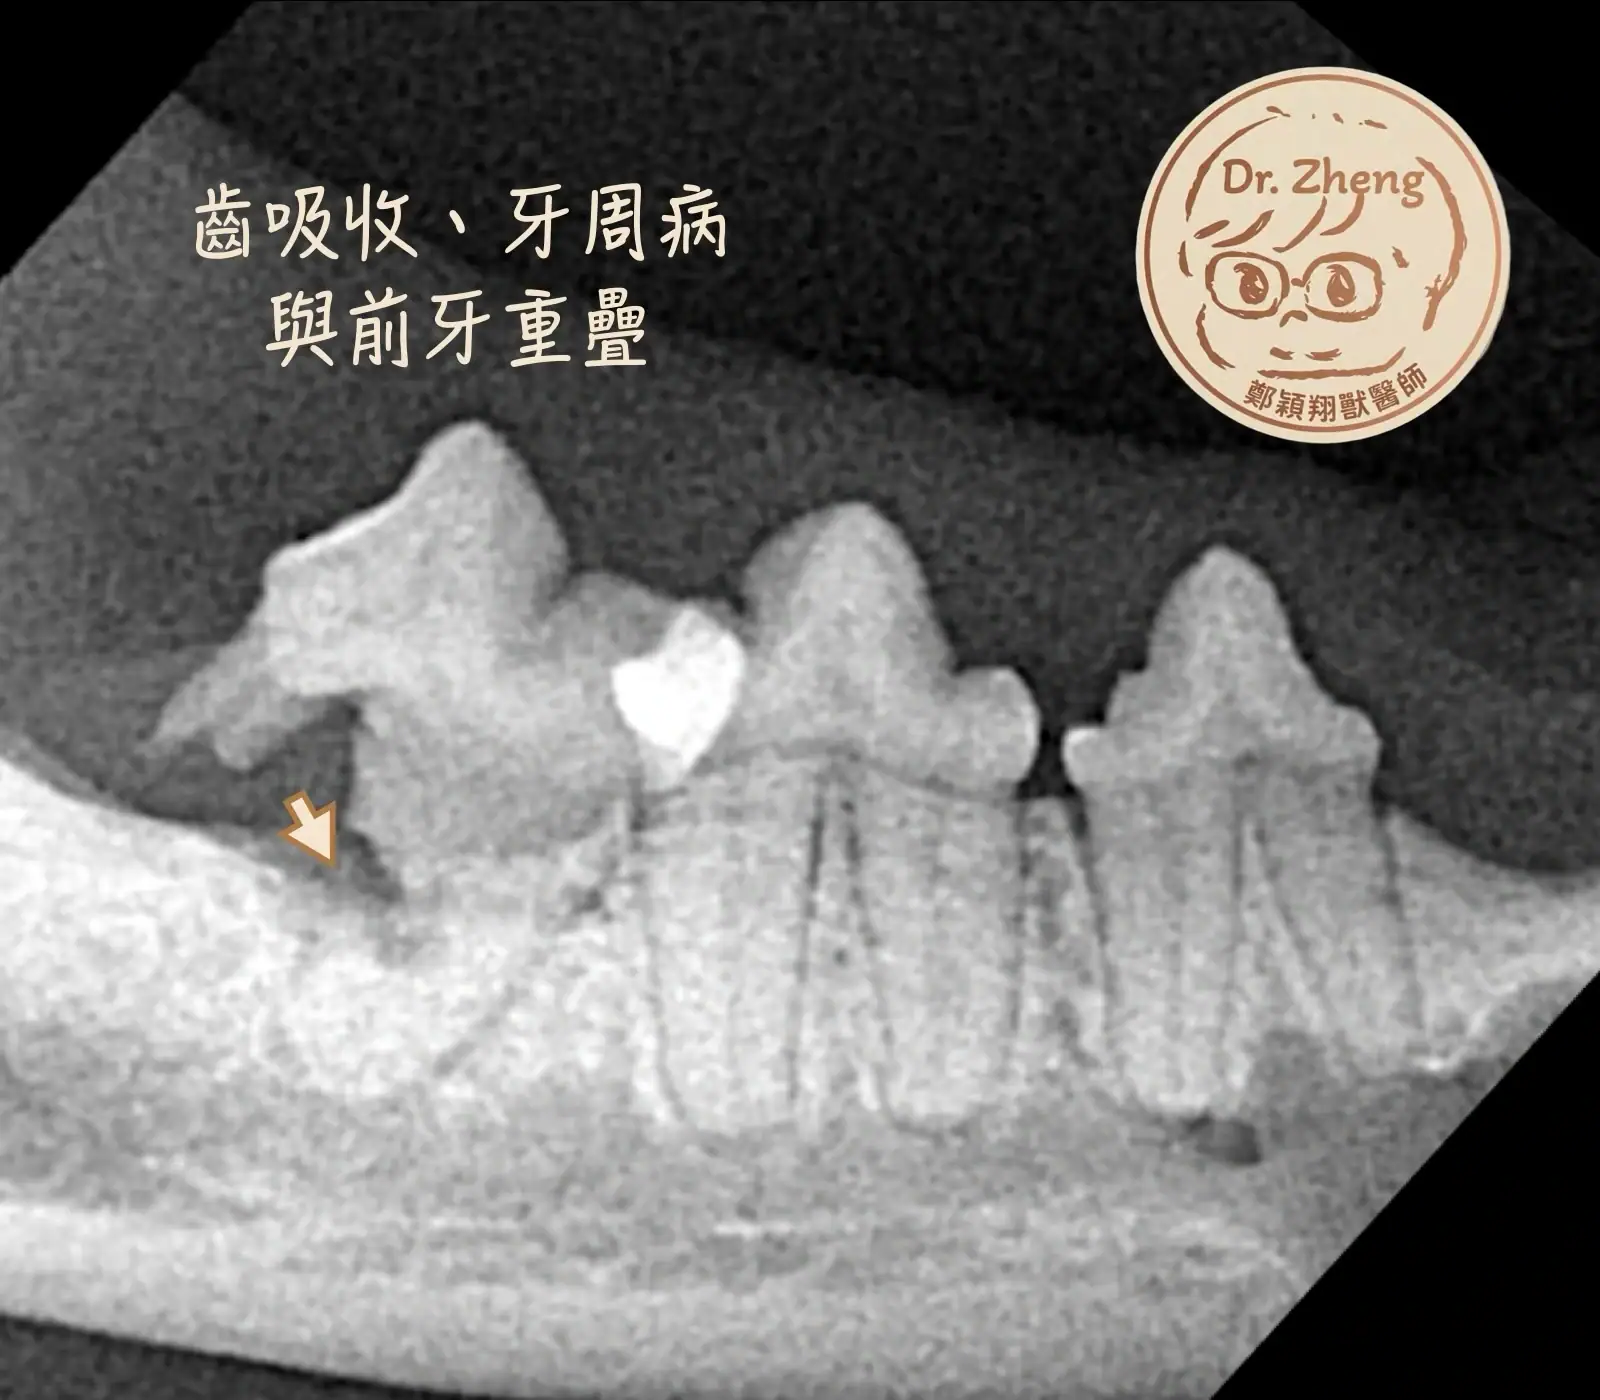

情境一:牙周病、貓齒吸收病灶

貓咪是齒吸收病灶的高風險群。這是一種牙齒會慢慢被身體吸收、非常疼痛的疾病。

貓咪的口腔,重疊問題在2D平面上會是個問題。CBCT 能在一次掃描中顯示全口所有牙齒,透過 3D 重建,能準確找出吸收病灶,避免遺漏,減少二次手術的機會。